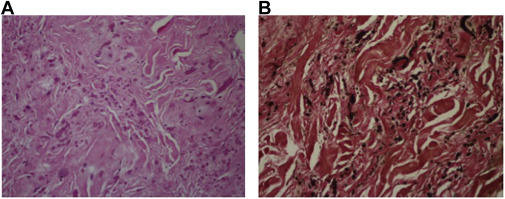

Macroscopically, ED is a hard tumor without a capsule and has uncertain boundaries that cannot be distinguished from the muscle and fat tissue around it (Fig. 3 ). Pathologically ED consists of abnormal elastic fibrils and fibroblasts spread in normal collagen fiber bundles (Fig. 4 ). None of the patients required blood transfusion.

|

Fig. 4. (A) Bent or globoid elastic fibers and rare fibroblasts are visible in imaging degenerated with eosinophilic thick collagen (H&E, ×200). (B) Extending and globoid elastic fibers observed using Verhoeff–van Giesons histochemical dye.